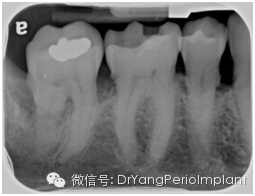

在牙周检查里,最常用的是根尖片(periapical view)和咬翼片(bitewing)有时候再加上全景片(panoramical view)

在读根尖片前,首先要确定拍摄的X光片质量,换句话说,这张根尖片有没有用于诊断的价值(diagnostic quality).

Prichard早在1972年就提出了判断根尖片质量的标准(Prichard:Advanced periodontal disease: surgical and prostheticmanagement, 2版)

1. 显示磨牙牙尖,无或略显示HE(Occlusal table, 中文字典里找不到这个字,唉!!)

2. 釉质,髓腔分明

3. 临面分开

4. 除非牙位异常,牙临面无重叠

达到诊断质量的根尖片(X光片取自笔者治疗过的病人)。

根尖片上看什么呢?

1. 骨量(bone level): (AAP 2015--Task Force Report,见美国牙周协会American Association of Periodontology 网页:https://www.perio.org/resources-products/clinical-scientific-papers.html

1有骨缺失(no bone loss)

2水平骨吸收(horizontal bone loss)

轻度:<15% 牙根长度,2-3 mm,

中度:16-30%, 3-5mm,

重度:> 30%, >5 mm

3垂直骨吸收(vertical bone loss) (1-, 2-, 3-壁牙周袋, 骨吸收占牙根长度比例)

2. 冠根比例(crown root ratio) (有利,可接受,不利的划分以1:1为界限)

3.牙周韧带宽度(Periodontal ligament width)(正常宽度大约0.2 mm

4. X线片上有无可见牙石(radiographically visible calculus)

5. 牙根形态 (root morphology): 锥形,柱形,长度,与临牙牙根关系

6. 根尖阴影(periapical radiolucency ) (+/-), 牙根吸收/合并/弯曲/多生牙根

7. 根干长度(root trunk length):

(3 mm)中等(4 mm), (5mm)—上颌

(2 mm)中等(3mm), (4 mm)—下颌

8. 根分叉阴影 (furcation radiolucency) (+/-)

9. 根分叉入口 (furcation entrance):根分叉箭头 (高度特异性)

10. 磨牙牙根分离度/融合度(root separation/fusion)

11. 牙槽骨硬板(lamina dura)

12. 临牙间牙釉质牙骨质分界差异(CEJ discrepancy)

13. 牙槽骨松质骨,病理变化 (cancellous bone and/or pathological changes)

14. 任何修复体(restoration)(是否有悬突,修复体边缘是否密合,修复体边缘是否侵犯生物宽度,边缘脊是否一致)